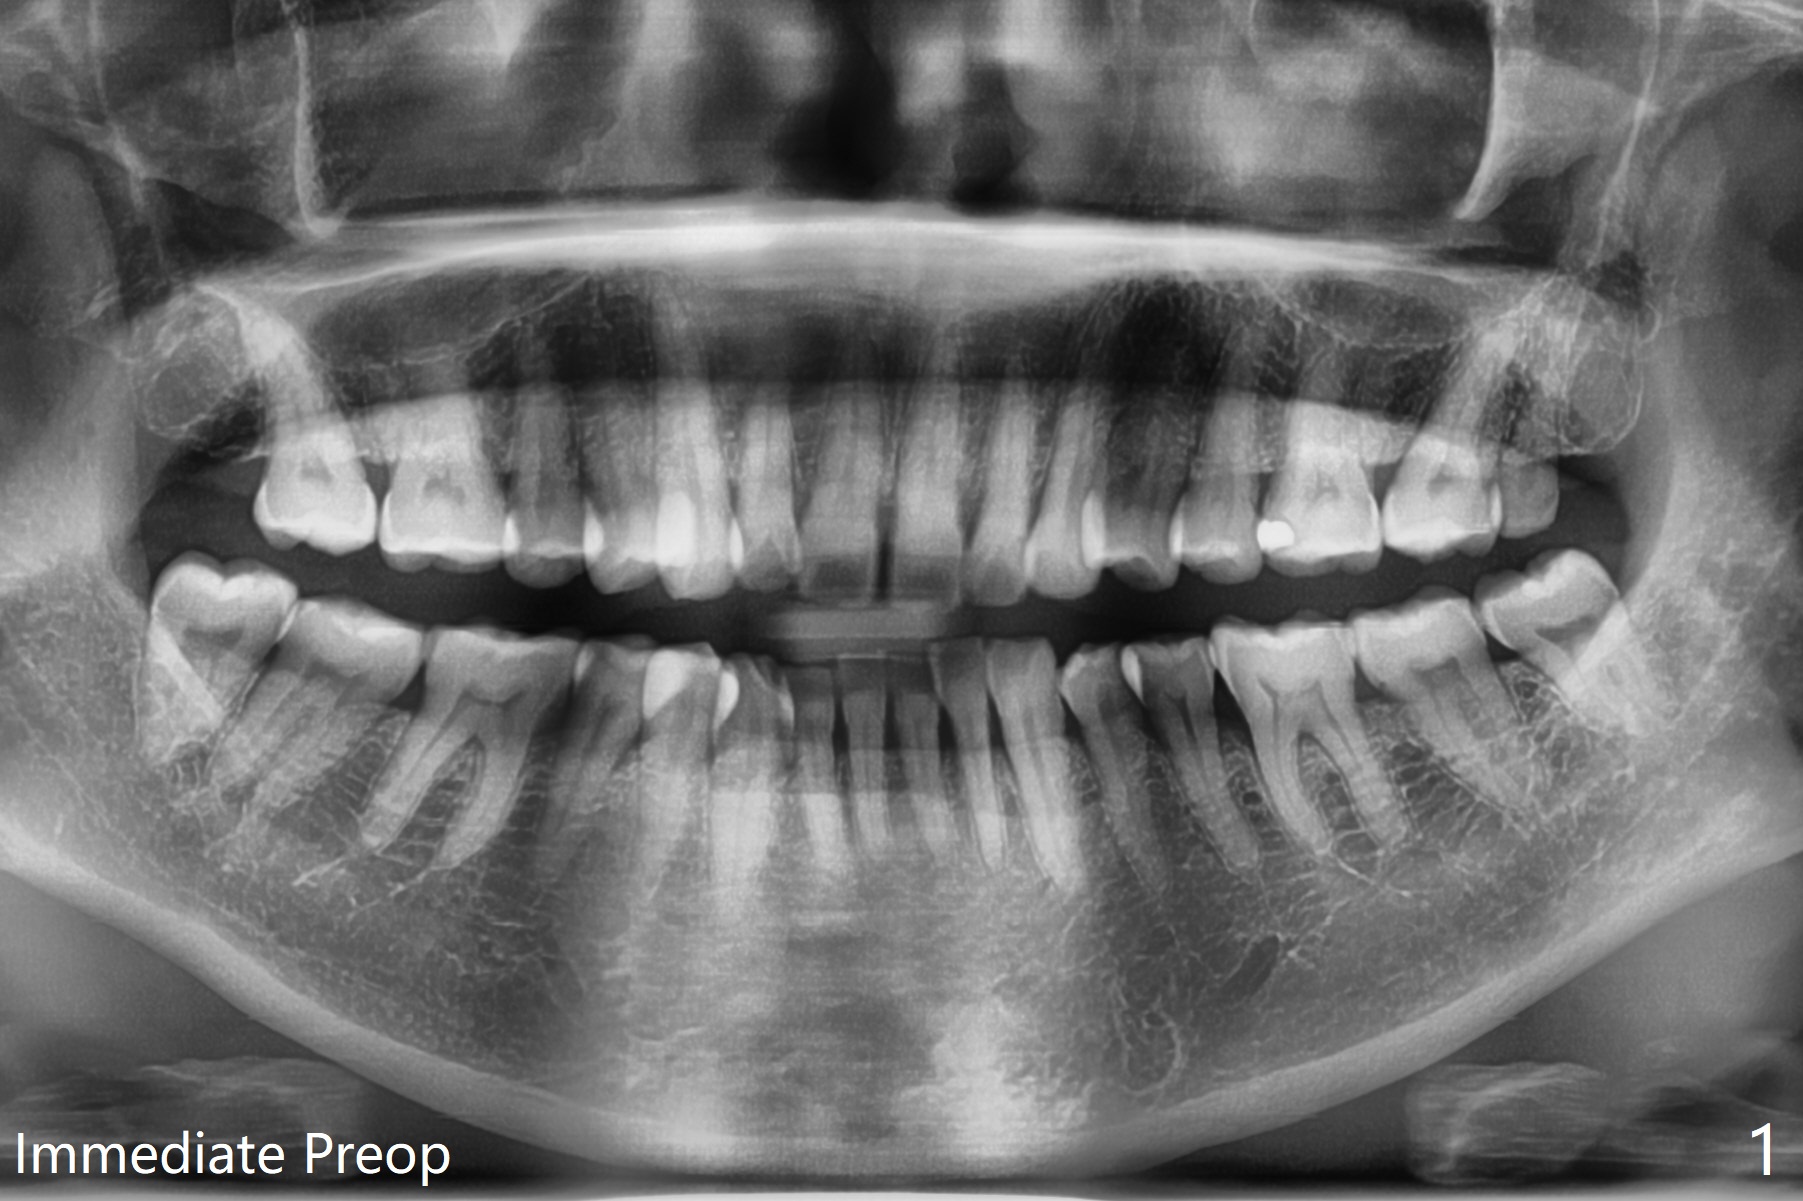

51岁女年终有多余的钱,想拔除左下智齿(早期龋齿),经过讨论,也同意拔除右下和左上智齿(图一)。看上去所有智齿拔除容易,但是右下第二,三磨牙之间骨板薄,不敢使用牙挺,怕的是松动第二磨牙,而单纯使用牙钳无法松动智齿,只好切开,颊侧去骨,形成purchase point,牙齿顺利拔除。左下智齿也采取同样方法拔除,之后下颌牙槽窝放置0.5毫升Bond Apatite和半块胶原塞,PGA多针缝合(图二),术后口服Amoxicillin。术后第四天左下出现典型干槽症症状,第七天就诊,缝线溶解,牙槽窝似乎是空的,生理盐水冲洗,改善不大,而右下缝线仍在,伤口愈合正常。拍摄局部全景片(图三),左下牙槽窝上半部好像失去骨水泥。疑问:局麻下,再次清创,放置粘性骨粉和PRF膜,能改善症状?伤口需要减张缝合(第一次和这次,periosteum underscoring)?